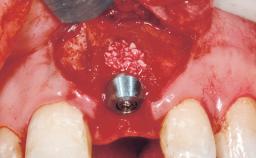

A 30-year-old female patient had lost tooth 21 and was referred to our clinic for consultation and treatment. Due to advanced apical infection, tooth 21 had been extracted two months earlier at another clinic and an acrylic-resin tooth had been bonded to the adjacent teeth. The patient desired implant treatment to avoid any damage to the adjacent natural teeth. While the patient had no history of any systemic disorder, she was a heavy smoker and exhibited medium to advanced periodontitis in the entire jaw. After the initial treatment to achieve a pocket probing depth of less than 4 mm and no bleeding on probing, a decrease in the height of the papillae mesial and distal to the extraction site and overall gingival recession were observed.

| # of Implants | 1 |

| Type of Implants | One-Piece|Reduced-Diameter |

| Bone Augmentation | Horizontal|Staged |

| Augmentation Materials | Autogenous chips|Membrane |